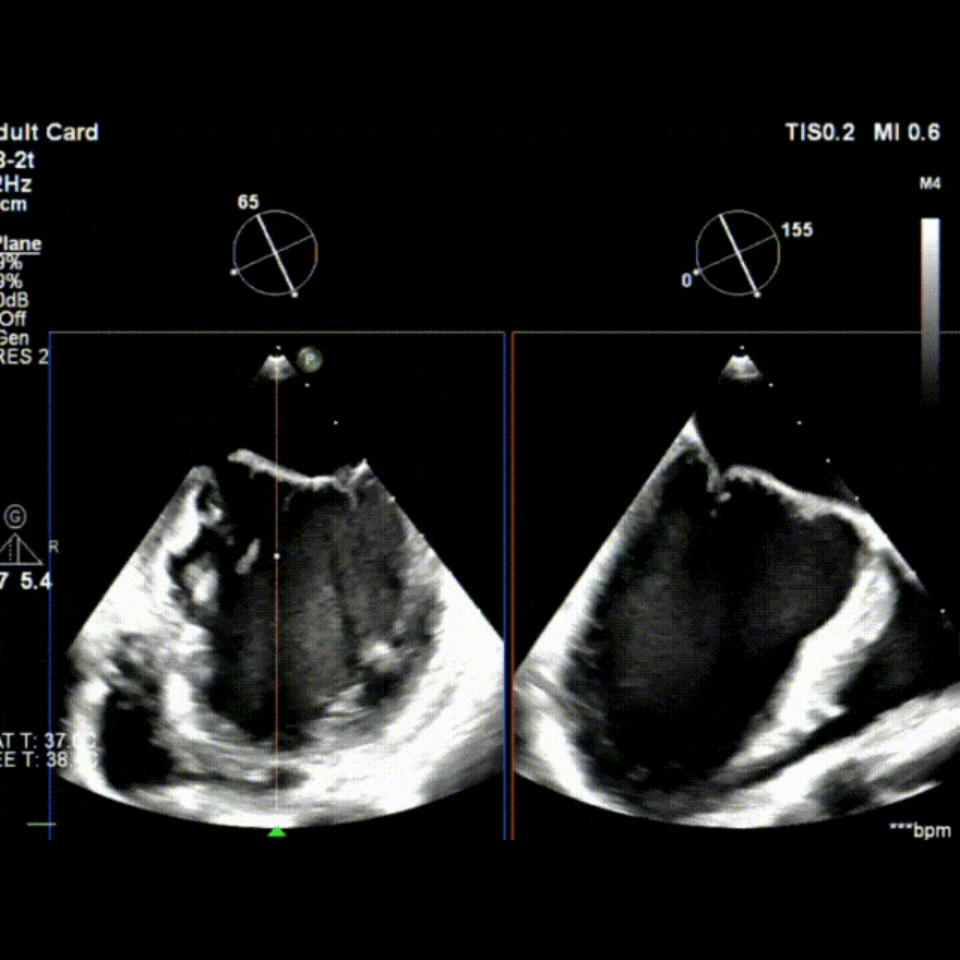

会议期间,张海波教授团队联合李伟教授完成了一例TA-TEER现场手术演示。患者为混合性二尖瓣反流(DMR+FMR),伴瓣环扩大、前瓣叶冗长、三区反流、后叶栓系及短小等复杂情况。术者在充分评估后选择置入双夹,手术获得圆满成功。现场专家就夹子型号选择、双夹放置位置及三区交界病变穿刺点等问题展开了深入讨论。

术前TEE影像

术中TEE影像